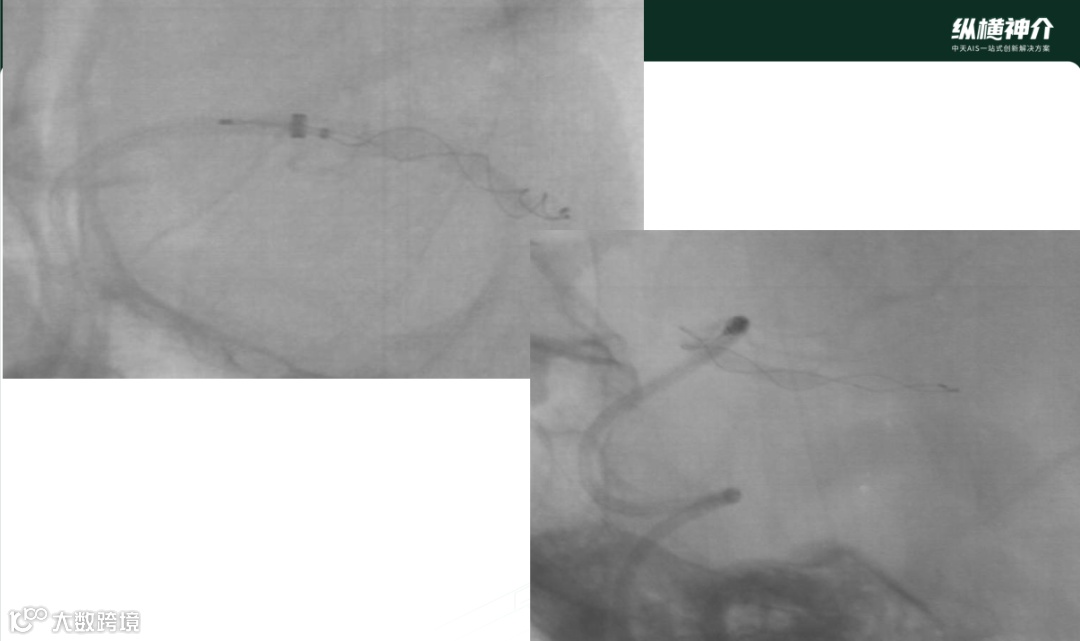

病例一

• 天弋®取栓支架显影性

• 一把即开通闭塞血管,达到mTICI3级血流再通